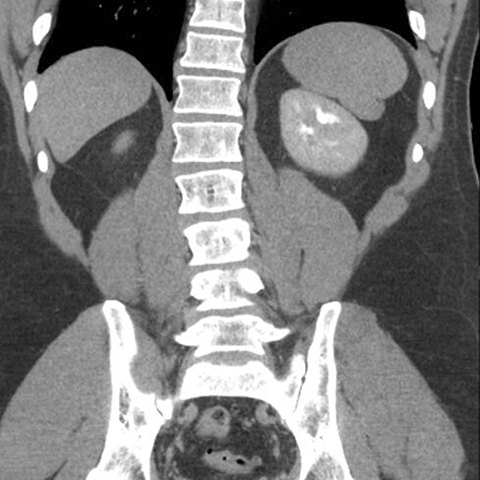

Normal spleen, coronal view (CT) [5 of 5]